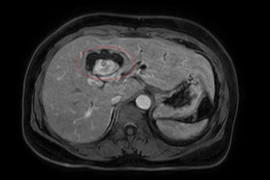

Bệnh nhân sẽ được chỉ định làm các xét nghiệm hình ảnh như siêu âm, CT scan hoặc MRI để theo dõi sự phát triển của khối u. Nếu khối u không tăng kích thước hoặc không gây ra triệu chứng, không cần can thiệp điều trị.

u-mau-trong-gan.jpg

U máu gan - Ảnh minh họa Bệnh viện Việt Đức